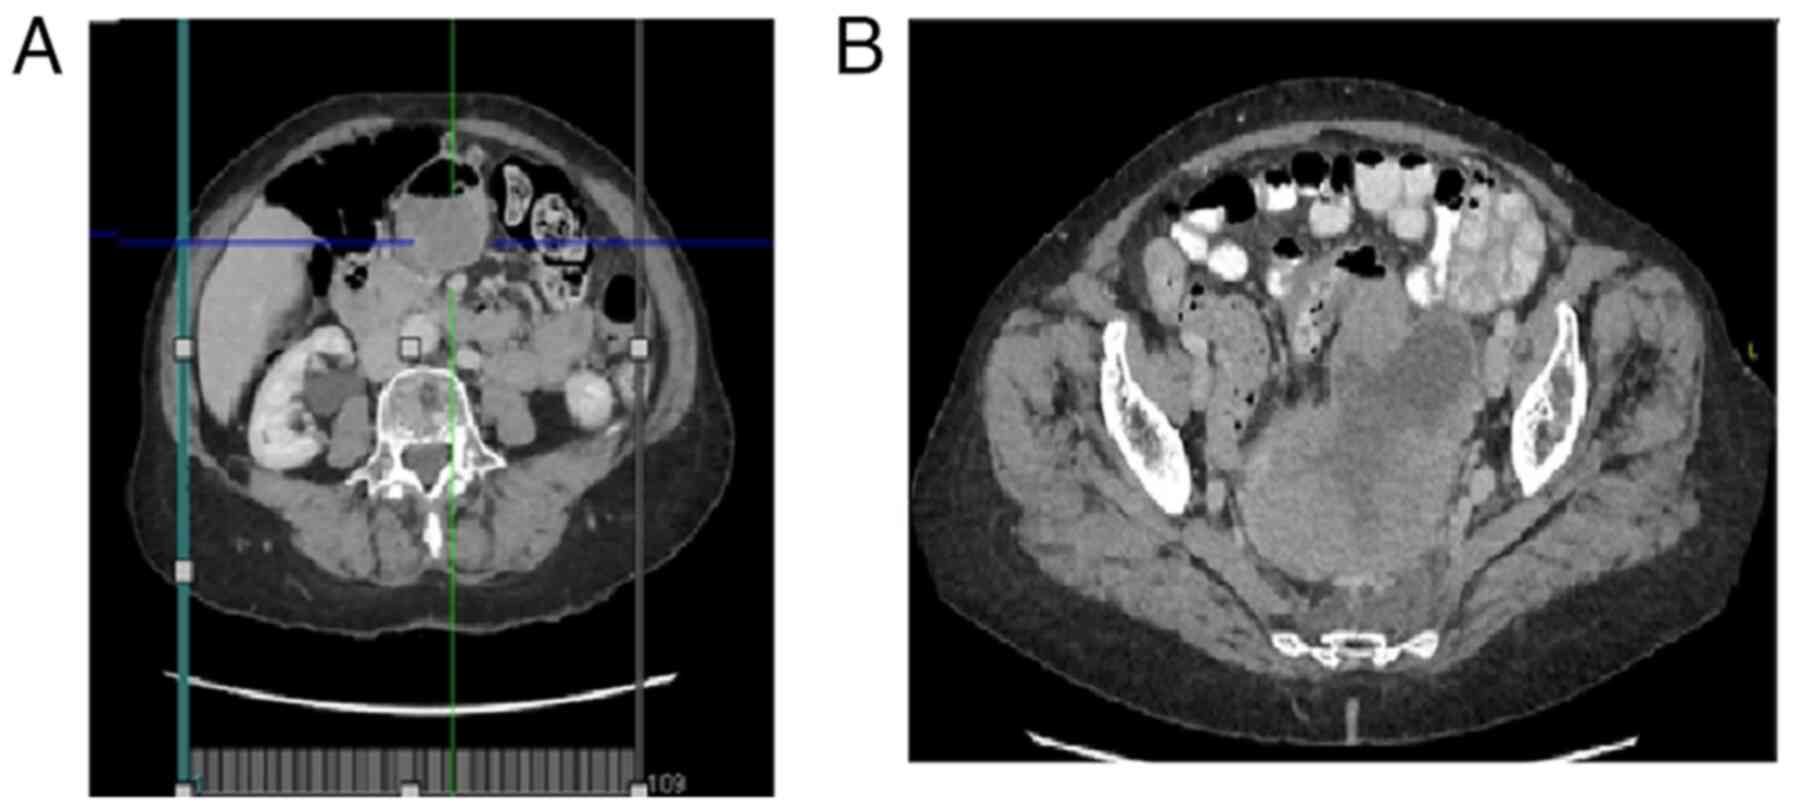

Uterine carcinosarcoma with intestinal involvement: A case report and literature review

Uterine carcinosarcoma (UCS) is a high‑grade endometrial cancer characterized by two components: Carcinomatous (epithelial) and sarcomatous (stromal tissue) elements. The present study describes a clinical case of this type of UCS and also provides a brief literature review of this type of tumor. A 72‑year‑old female visited the emergency department of the authors' hospital with pain in the hypogastric region, intestinal dysrhythmia since 3 months prior, fever and a palpable abdominal mass. Laboratory test results revealed sepsis and mild anemia and an imaging test revealed a large uterine tumor with wide areas of necrosis and adenopathies. As determined by the multidisciplinary committee, surgery was considered the main treatment option and this was performed with no incidences. Carcinosarcoma is a rare tumor, which most frequently occurs in older women. The diagnosis is based on symptoms and imaging tests, such as ecography and scans. The gold standard of treatment is surgery, although it is possible that other types of therapies, such as chemotherapy and radiotherapy may also be effective, depending on the tumor stage. On the whole, the prognosis of patients with this type of tumor is poor, with a low survival rate, even in earlier stages due to its malignant component and the possibility for metastasis. Surgery is the optimal treatment for this type of tumor, if this is possible, always individualizing patients.

Figure 1

Figure 2